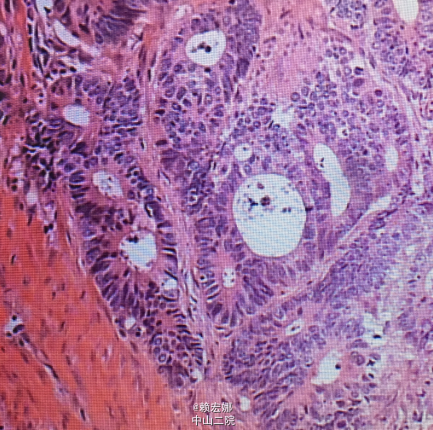

患者肺癌诊断明确,术前检查未见明显禁忌症,胸腔镜下行左下肺癌根治术,手术顺利,术后病理:1、(左下肺)浸润性肺腺癌,实体为主型;2、支气管及肺切缘未见癌残留;3、(5 7 9 10 11组)淋巴结未见癌转移(0/4 0/5 0/2 0/1 0/1).术后予重症监护,抗感染、营养支持等对症支持治疗。